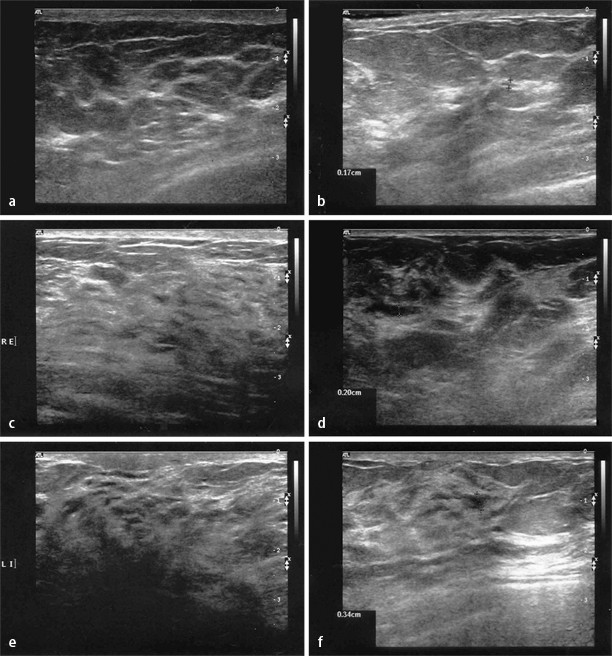

Gutartig Oder Bosartig Brustkrebsdiagnostik Verbessern Durch Weiterentwickelten Ultraschall Labo Online